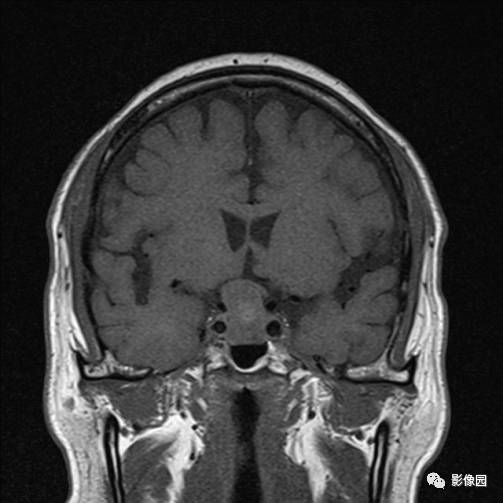

独孤求败:诊断为垂体瘤,蝶鞍扩大,鞍底下陷,鞍内见突向鞍上生长的团块状异常信号,T1WI呈等及稍高信号,T2WI呈等及低信号,增强扫描病灶呈明显不均匀强化;垂体柄显示不清,视交叉受压上抬。

bnzhang07:这是典型的垂体大腺瘤,垂体大腺瘤冠状扫描显示肿瘤呈哑铃状或“束腰征”,这是由于肿瘤伸于鞍上,中部受鞍隔束缚的原因。